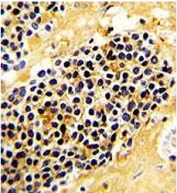

IHC testing of FFPE human kidney carcinoma with NKG2A antibody. HIER: steam section in pH6 citrate buffer for 20 min and allow to cool prior to staining.